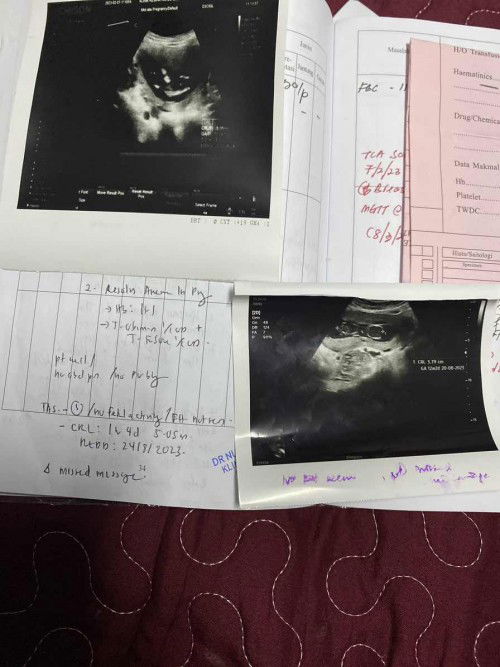

Checkup hari ni doktor beritahu dah xde pergerakan baby dan jantung pun da xdetect..mmg terkejut ni first time gugur, anak dah ada dua 6tahun dgn 4tahun..mmg merancang nak tambah lg.tapi kite hnya mampu merancang, Allah yang menentukan. Mgkin ini bukan rezeki kami lg, ada hikmah semua yg berlaku. Usia kandungan 14w3d, tapi baby stop develop pada usia 12w2d..start malam ni ada sakit perut mcm senggugut n da nmpk darah trun…ya Allah hati ni mmg sedih sgt tapi tetap kena terima ujian yg Allah beri. Semoga Allah permudahkan janin keluar secara semulajadi tanpa ada yg tertinggal dlm rahim..doakan sy ye mummy2 semua..kalau ada yg boleh share tips mcm mne nk bagi janin keluar semulajadi boleh la share..tq mummy semua. Sy doakn mummy2 lain yg prgnant semoga sihat sentiasa sehingga melahirkan